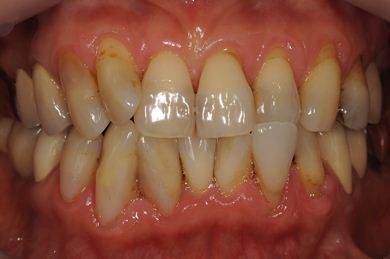

抜歯即日スピードインプラント+セラミック治療

| 治療内容 | インプラント2本(抜歯即日スピードインプラント)、ハイブリッドセラミッククラウン5本(セラミック用土台2本)、ハイブリッドセラミックインレー1本 | ||||||||||||||||||||||||||||||||